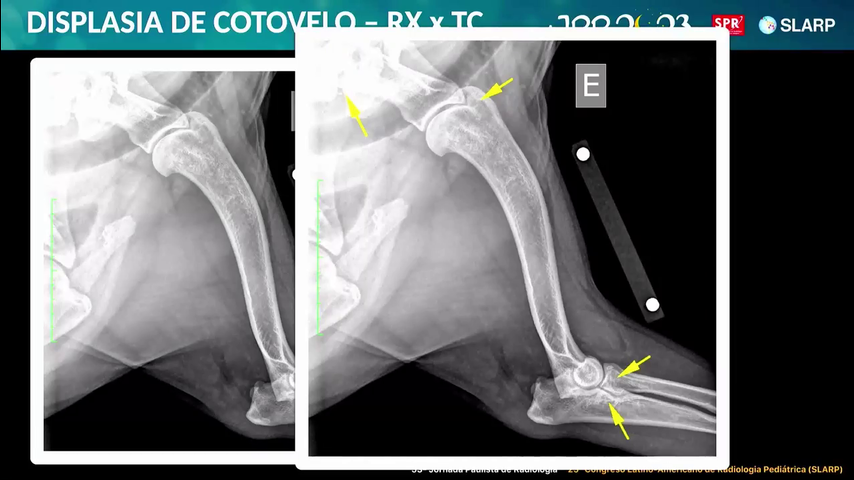

Discussão de Caso Multimodal RX + TC ...

Discussão de Caso Multimodal RX + TC - Displasia de Cotovelo